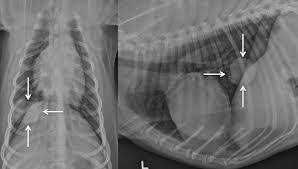

Lung tumors are relatively rare in dogs, accounting for only 1% of all cancers diagnosed.

When your dog is nearing the end of his/her life, the emotional weight that falls upon you can be tremendous. Dog cancers vary greatly in the speed at which they spread and grow, how easy they are to treat, and the predicted life expectancy for dogs diagnosed with that particular cancer. The prognosis for primary lung cancer varies, and can be very difficult to predict for an individual dog. However, if surgery is possible and the tumors are completely removed, a total remission may be recorded. Similar to other cancers in dogs, it is seen more often in dogs over seven years of age. If you were to look at some of the other statistics above, you can see that if you had a dog who underwent spleen removal 8 weeks ago, is not on chemo, and is still maintaining, you are beating the odds. On average, lung cancer in dogs will metastize in 2 to 10 months, depending on when the tumor is detected and what treatment options are available or the strength of the animal to fight the disease. The life expectancy of a dog diagnosed with lung cancer can be up to 22 months, depending on the type of tumor and on the treatment the dog undergoes. If your dog has a single, small tumor, the procedure is often an effective method of treatment. A dog's life expectancy at this point can be hours to days. Lung tumors are relatively rare in dogs, accounting for only 1% of all cancers diagnosed. Many of us view our dog as a beloved member of the family to whom we have made a commitment. Typical (doubling time of 183 to 365 days):

Amazingly, dogs can function normally even with up to 50 percent of their total lung volume removed. When tumors are in the early stage, can undergo surgical removal, and have not even come close to spreading to other parts of the body, dogs are expected to live for roughly twenty months. Lung tumors are relatively rare in dogs, accounting for only 1% of all cancers diagnosed. The best prognosis is seen in dogs with solitary lesions that are less than 2 inches in diameter. If your dog is 8, and the average lifespan for his weight and breed is 10 years, and your veterinarian tells you that his survival time for his cancer is about 18 months to two years, and calls that a long time, he's right from a medical perspective.